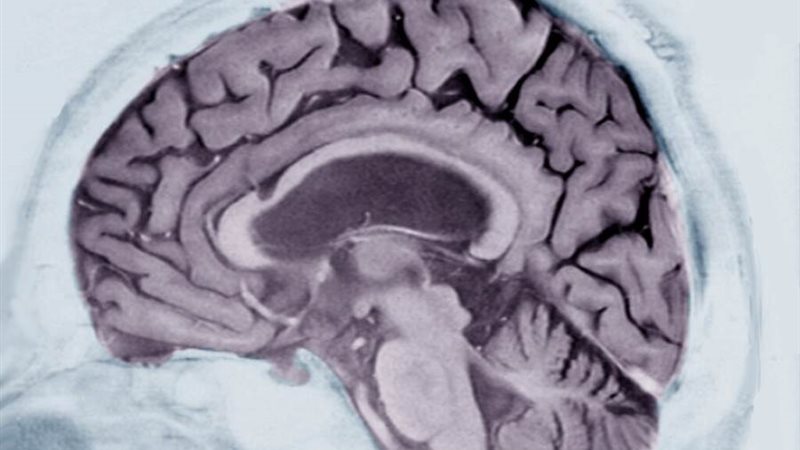

قبل سنوات من ظهور الأعراض؟ ووفقًا لدراسة جديدة أجراها باحثو IBM، فإن الإجابة هي نعم. وهم وآخرون يقولون إن مرض الزهايمر ما هو إلا البداية. الأشخاص المصابون بمجموعة متنوعة من الأمراض العصبية لديهم أنماط لغوية مميزة، كما يعتقد الباحثون، قد تكون بمثابة علامات إنذار مبكر لأمراضهم. بالنسبة لدراسة مرض الزهايمر، نظر الباحثون إلى مجموعة من 80 رجلًا وامرأة في الثمانينيات من العمر – نصفهم مصابون بمرض الزهايمر والآخرون لم يفعلوا ذلك. ولكن، قبل سبع سنوات ونصف، كان كل شيء طبيعيًا من الناحية المعرفية. كان الرجال والنساء مشاركين في دراسة فرامنجهام للقلب، وهي جهد بحثي فيدرالي طويل الأمد يتطلب اختبارات بدنية ومعرفية منتظمة.

كجزء من ذلك، أجروا اختبارًا كتابيًا قبل أن يصاب أي منهم بمرض الزهايمر الذي يطلب من المشاركين وصف رسم لصبي يقف على كرسي غير مستقر ويصل إلى جرة بسكويت على رف عال بينما امرأة، تعيدها إليه، غافل عن بالوعة فيضان.

كان الرجال والنساء مشاركين في دراسة فرامنجهام للقلب، وهي جهد بحثي فيدرالي طويل الأمد يتطلب اختبارات بدنية ومعرفية منتظمة. كجزء من ذلك، أجروا اختبارًا كتابيًا قبل أن يصاب أي منهم بمرض الزهايمر الذي يطلب من المشاركين وصف رسم لصبي يقف على كرسي غير مستقر ويصل إلى جرة بسكويت على رف مرتفع بينما تقوم امرأة بإعادتها إليه، غافل عن بالوعة فيضان وقام الباحثون بفحص استخدام الكلمات من خلال برنامج ذكاء اصطناعي يبحث عن الاختلافات الدقيقة في اللغة.

وتوقع البرنامج، بدقة 75٪، من سيصاب بمرض الزهايمر، وفقًا للنتائج التي نُشرت مؤخرًا في مجلة The Lancet Journal EClinicalMedicine.

وكان باحثو مرض الزهايمر مفتونين، قائلين إنه عندما تكون هناك طرق لإبطاء المرض أو إيقافه -وهو هدف لا يزال بعيد المنال حتى الآن -سيكون من المهم إجراء اختبارات بسيطة يمكن أن تحذر، في وقت مبكر، من أنه بدون تدخل سيطور الشخص التقدم أمراض الدماغ.